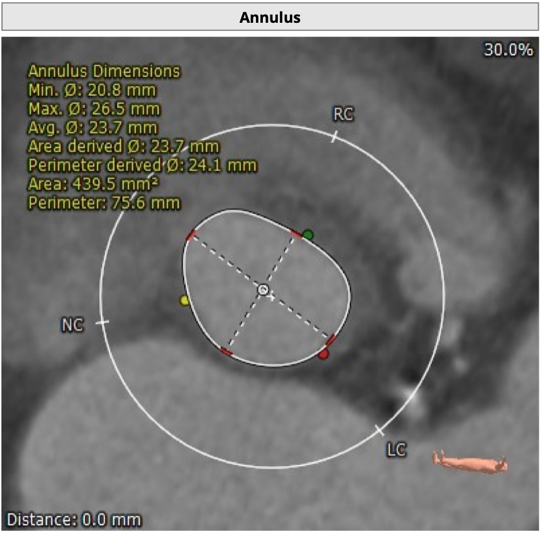

CT 数据显示该患者为三叶式主动脉瓣

主动脉瓣瓣环周长75.6mm,周长径24.1mm;

LVOT 周长 74.1mm,周长径23.6mm;

SOV:28.5mm*31.6mm*29.4mm;

STJ 周长 93.9mm;

HU850:87mm³;

瓣环水平夹角52度。